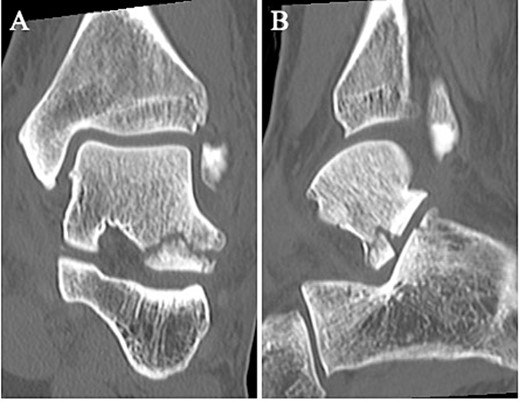

A 24-year-old male basketball player presented to our hospital complaining of left lateral ankle pain during a cutting motion. His height, weight, and body mass index were 172 cm, 64.0 kg, and 21.6 kg/m2, respectively, and he had no history of previous medical conditions. On his first visit to our hospital, he could not walk due to pain. Physical examination revealed swelling, ecchymosis, and tenderness at the lateral aspect of his left ankle. The American Orthopedic Foot and Ankle Society (AOFAS) score was 32 out of 100 points. Plain radiographs of the left ankle showed no abnormal findings in the anteroposterior view, but a fracture line was discovered at the base of the lateral process of the talus in the lateral view (Fig. 1). Non-contrast computed tomography (CT) showed a simple fracture line that extending from the talofibular articular surface down to the posterior talocalcaneal articular surface of the subtalar joint. In addition, the bone fragment was displaced >2 mm (Fig. 2). The patient was diagnosed with Type I LPFT and underwent surgical treatment.

Plain radiographs of the left ankle showed no abnormal findings in the anteroposterior (A) view, but a fracture line was discovered at the base of the lateral process of the talus in the lateral (B) view.

Non-contrast CT showed a simple fracture line that extending from the talofibular articular surface down to the posterior talocalcaneal articular surface of the subtalar joint in the coronal (A) and sagittal (B) views.